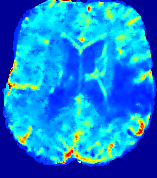

LesionRefer to captionRefer to captionRefer to captionRefer to captionRefer to captionRefer to caption𝐕rgbsubscript𝐕𝑟𝑔𝑏{\bf{V}}_{rgb}Refer to captionRefer to captionRefer to captionRefer to captionRefer to captionRefer to caption𝐕2subscriptnorm𝐕2{\|\bf{V}}\|_{2}Refer to captionRefer to captionRefer to captionRefer to captionRefer to captionRefer to captionRefer to caption3.53.53.52.82.82.82.12.12.11.41.41.40.70.70.70.00.00.0(mm/s)𝑚𝑚𝑠(mm/s)D𝐷DRefer to captionRefer to captionRefer to captionRefer to captionRefer to captionRefer to captionRefer to caption0.0200.0200.0200.0160.0160.0160.0120.0120.0120.0080.0080.0080.0040.0040.0040.0000.0000.000(mm2/s)𝑚superscript𝑚2𝑠(mm^{2}/s)Slice #1Slice #2Slice #3Slice #4Slice #5Slice #6

Figure 4: PIANO feature maps for another patient in the ISLES 2017 training set, where the lesion is located in the right hemisphere. Top row: segmented stroke lesion region (white) on different slices. The corresponding slices for the PIANO feature maps are shown in the following rows.

For a better insight into an estimated velocity field 𝐕𝐕{\bf{V}} and diffusion field 𝐃𝐃{\bf{D}}, we compute the following maps: (1) 𝐕rgbsubscript𝐕𝑟𝑔𝑏{\bf{V}}_{rgb}: Color-coded orientation map of 𝐕=(Vx,Vy,Vz)T𝐕superscriptsuperscript𝑉𝑥superscript𝑉𝑦superscript𝑉𝑧𝑇{\bf{V}}=(V^{x},V^{y},V^{z})^{T}, obtained by normalizing 𝐕𝐕{\bf{V}} to unit length and mapping its 3 components to red, green, blue respectively; (2) 𝐕2subscriptnorm𝐕2\|{\bf{V}}\|_{2}: 222 norm of 𝐕𝐕{\bf{V}}; (3) D𝐷D: scalar field in Eq. 5.

Fig. 3 and Fig. 4 show the PIANO feature maps estimated from two ISLES 2017 patients: all are highly consistent with the lesion in both cases. Details of the blood flow trajectories are revealed in 𝐕rgbsubscript𝐕𝑟𝑔𝑏{\bf{V}}_{rgb} by the ridged patterns and the sharp changes of colors in the unaffected (right) hemisphere, while the flat patterns appearing within the lesion provide little directional information about the velocity and indicate low velocity magnitudes. Velocity magnitudes are more directly visualized via 𝐕2subscriptnorm𝐕2\|{\bf{V}}\|_{2}, from which one can easily locate the lesion where 𝐕2subscriptnorm𝐕2\|{\bf{V}}\|_{2} is low. D𝐷D also indicates lower diffusion values in the lesion, though with less contrast potentially due to the fact that it captures the accumulated effect of CA diffusion at the voxel-level.